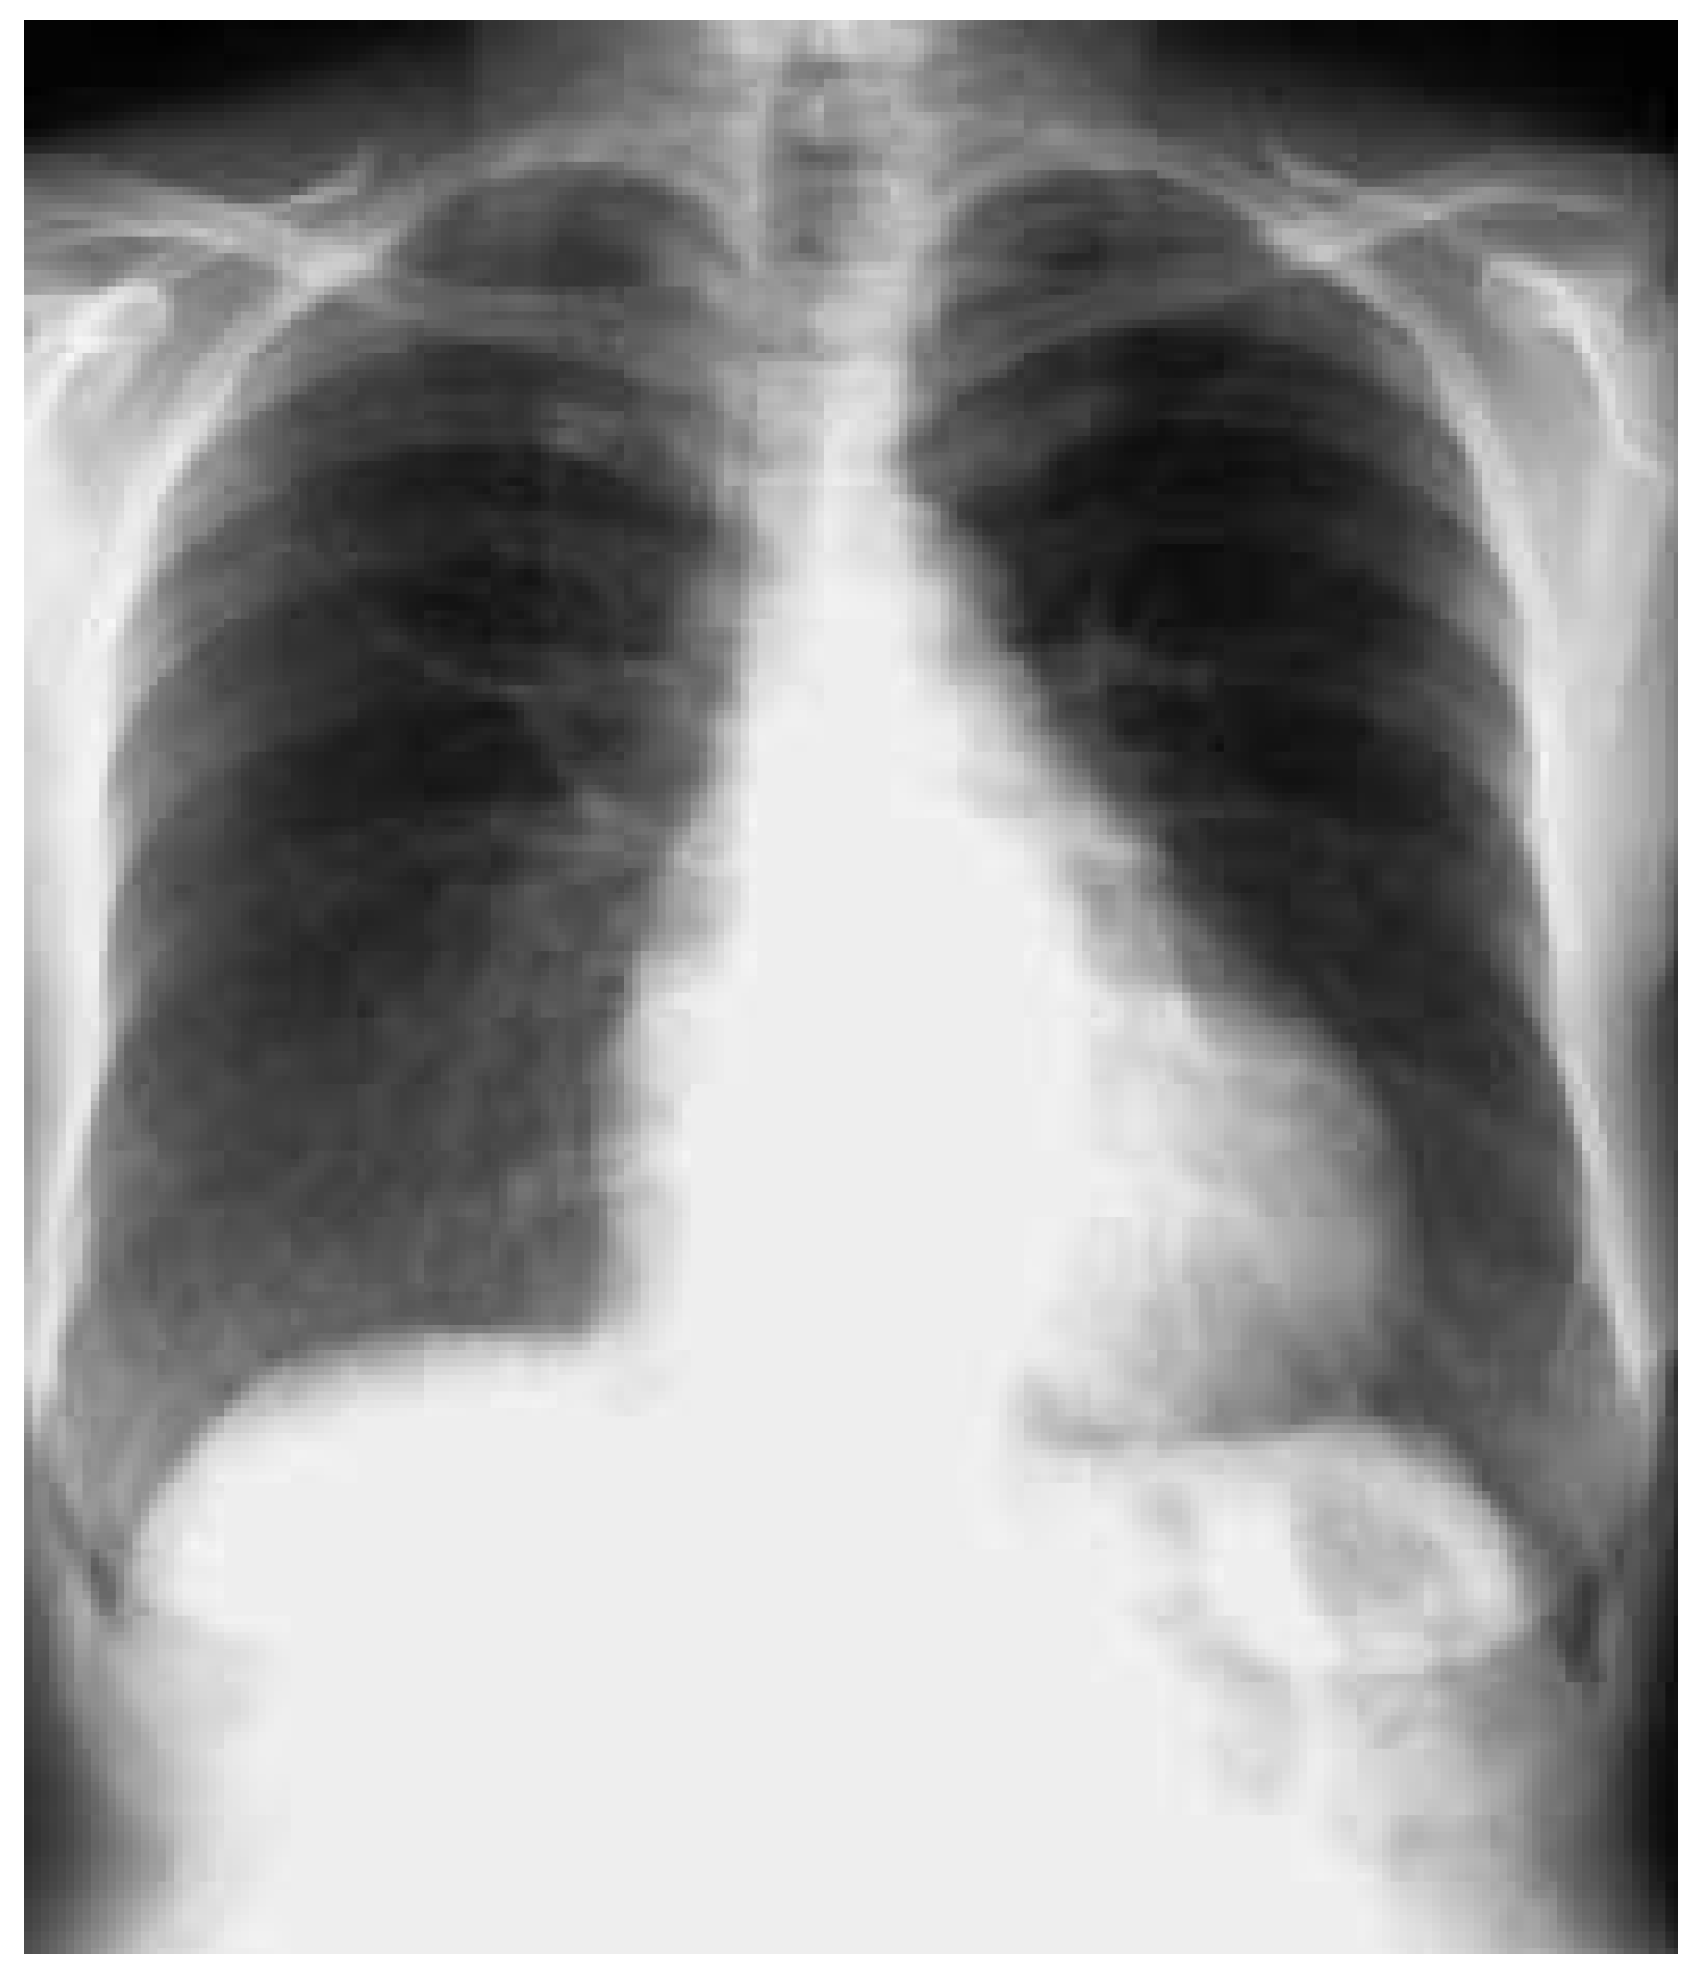

Zusammenfassend bestand eine Amiodarone-induzierte Pneumopathie, die auf die Steroidtherapie aussergew hnlich gut ansprach (Abb. 3). Infolge des verbreiteten Einsatzes des Medikamentes ist vermehrt mit Nebenwirkungen zu rechnen, auch in der niedrigeren Dosierung von 200 mg tgl. [1,2]. Wenn immer m glich, sollte auf den Einsatz von Amiodarone zur alleinigen Frequenzkontrolle beim Vorhofflimmern verzichtet werden. Bei Auftreten einer pulmonalen Verschlechterung unter Amiodarone-Therapie ist immer an diese schwere Form der Nebenwirkung zu denken und das Amiodarone abzusetzen oder durch eine alternative antiarrhythmische Behandlungsform zu ersetzen. Steroide zur Behandlung der Amiodarone-induzierten Pneumopathie sind umstritten. Bei unserer Patientin f hrte sie schnell zu einer deutlichen Verbesserung der Symptome wie auch des radiologischen Befundes.

Abbildung 3. Thorax-Röntgenbild bei Austritt.